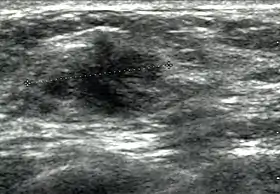

![]() Cancer ultrasound image | |

Breast ultrasound is a medical imaging technique that uses medical ultrasonography to perform imaging of the breast. It can be performed for either diagnostic or screening purposes[1] and can be used with or without a mammogram.[2] In particular, breast ultrasound may be useful for younger women who have denser fibrous breast tissue that may make mammograms more challenging to interpret.[3]

Elastography is a type of ultrasound examination that measures tissue stiffness and can be used to detect tumours.[6] Breast ultrasound is also used to perform fine-needle aspiration biopsy and ultrasound-guided fine-needle aspiration of breast abscesses.[7]